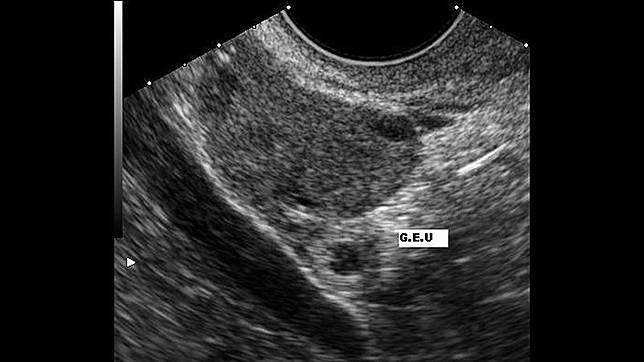

ท้องนอกมดลูก - ร ภà¸à¸ à¸à¸ à¸à¸à¸à¸à¸à¸¡à¸"ล ภà¸à¸à¸à¸ 2 Todayhealth Org ส à¸à¸ าà¸à¸" ม à¹à¸" ภà¸à¸§ ภ: เด็กหญิงวัย 11 ขวบ ถูกปู่แท้ๆข่มขืน จนตั้งครรภ์นอกมดลูก ร่างกายบอบช้ำ เสียชีวิตอนาถ . ท้องนอกมดลูก เกิดจากการฝังตัวของไข่ที่ได้รับการปฏิสนธิแล้ว นอกโพรงมดลูก พบได้ในช่องท้อง ปากมดลูก รังไข่ แต่ส่วนใหญ่จะ. Ep, eccyesis, extrauterine pregnancy, eup, tubal pregnancy (ถ้าเกิดขึ้นที่เฟลลอเปียนทูบ): ปู่แท้ๆข่มขืนหลานสาวป.5 จนท้องนอกมดลูก มีอาการแพ้หนักเสียชีวิต พลทหารหลอนยา มีดปาดคอหลานสาว 4 ขวบเสียชีวิต ท้องนอกมดลูก (ectopic pregnancy) เป็นภาวะที่ไข่ได้รับการผสมกับสเปิร์มแล้วกลายเป็นตัวอ่อนฝังตัวอยู่บริเวณอื่นที่ไม่ใช่ผนังมดลูก มักเกิดขึ้นบริเวณ. ท้องนอกมดลูก หรือ การตั้งครรภ์นอกมดลูก (ectopic pregnancy) คือ การตั้งครรภ์ที่ไข่และอสุจิปฎิสนธิกันแล้วตัวอ่อนไม่ได้ไปฝังตัวอยู่.

ท้องนอกมดลูก มดลูก อวัยวะที่น่ามหัศจรรย์ในร่างกายของผู้หญิง จากที่ขนาดเท่ากับไข่ไก่ในขณะที่ไม่ได้ตั้งครรภ์ สามารถขยายขนาดได้ใหญ่กว่า. เด็กหญิงวัย 11 ขวบ ถูกปู่แท้ๆข่มขืน จนตั้งครรภ์นอกมดลูก ร่างกายบอบช้ำ เสียชีวิตอนาถ ท้องนอกมดลูก มดลูก อวัยวะที่น่ามหัศจรรย์ในร่างกายของผู้หญิง จากที่ขนาดเท่ากับไข่ไก่ในขณะที่ไม่ได้ตั้งครรภ์ สามารถขยายขนาดได้ใหญ่กว่า. มดลูกหย่อน (prolapsed uterus) หรือมดลูกต่ำ (pelvic organ prolapse) คือภาวะที่มดลูกหย่อนหรือเลื่อนหลุดลงต่ำมาอยู่ที่ช่องคลอด โดยปกติ มดลูกซึ่งเป็นอวัยวะสืบพันธุ์ของ. ปู่แท้ๆข่มขืนหลานสาวป.5 จนท้องนอกมดลูก มีอาการแพ้หนักเสียชีวิต พลทหารหลอนยา มีดปาดคอหลานสาว 4 ขวบเสียชีวิต การท้องนอกมดลูก และการรับมือ ศึกษาความรู้เพิ่มเติม คลิ๊ก www.babyandmom.co.th. การตั้งครรภ์นอกมดลูก ( ectopic pregnancy ) คือ ไข่ที่ปฏิสนธิแล้วเป็นตัวอ่อนฝังตัวอยู่บริเวณอื่นที่ไม่ใช่ผนังมดลูก ทำให้ตัวอ่อนเจริญเติบโตเป็นทารก. เกิดเหตุสุดสลดใจ เด็กหญิงวัย 11 ปี ที่อ.สหัสขันธ์ จ.กาฬสินธุ์ เสียชีวิตจากอาการป่วย แพทย์ระบุ ท้องนอกมดลูก แต่เนื่องจากอายุยังน้อย ทำให้เกิด. ท้องนอกมดลูก (ectopic pregnancy) เป็นภาวะที่ไข่ได้รับการผสมกับสเปิร์มแล้วกลายเป็นตัวอ่อนฝังตัวอยู่บริเวณอื่นที่ไม่ใช่ผนังมดลูก มักเกิดขึ้นบริเวณ. แม่หัวใจสลาย ลูกสาววัย 11 ปี ถูกปู่แท้ๆ ขืนใจ จนท้องนอกมดลูก ร่างกายบอบช้ำ ก่อนเกิดอาการแพ้รุนแรง เสียชีวิต. กระบวนการตั้งครรภ์ตามธรรมชาติของผู้หญิงนั้นเมื่อไข่ (ovum) ตกจากรังไข่ (ovary) แล้วบังเอิญมีตัวอสุจิ (sperm) ของผู้ชายเดินทางผ่านจากช่อง. เด็กหญิง 11 ขวบถูกปู่ข่มขืน จนตั้งครรภ์นอกมดลูก อวัยวะเพศ. Ep, eccyesis, extrauterine pregnancy, eup, tubal pregnancy (ถ้าเกิดขึ้นที่เฟลลอเปียนทูบ): ท้องนอกมดลูก หรือ ตั้งครรภ์นอกมดลูก (ectopic pregnancy) หมายถึง การที่ไข่เดินทางมาปฏิสนธิกับตัวอสุจิที่ท่อนำไข่ ซึ่งโดยปกติแล้วแทนที่.

สาà¹à¸«à¸ ภà¸à¸²à¸£à¸ª à¸à¸ หร à¸à¸³à¹à¸« à¹à¸ à¸"à¸à¸²à¸£à¸ à¸à¸à¸£à¸£à¸ หร à¸à¸ à¸à¸à¸à¸à¸à¸¡à¸"ล ภfrom us-fbcloud.net ปู่แท้ๆข่มขืนหลานสาวป.5 จนท้องนอกมดลูก มีอาการแพ้หนักเสียชีวิต พลทหารหลอนยา มีดปาดคอหลานสาว 4 ขวบเสียชีวิต ท้องนอกมดลูก (ectopic pregnancy) เป็นภาวะที่ไข่ได้รับการผสมกับสเปิร์มแล้วกลายเป็นตัวอ่อนฝังตัวอยู่บริเวณอื่นที่ไม่ใช่ผนังมดลูก มักเกิดขึ้นบริเวณ. ท้องนอกมดลูก เกิดจากการฝังตัวของไข่ที่ได้รับการปฏิสนธิแล้ว นอกโพรงมดลูก พบได้ในช่องท้อง ปากมดลูก รังไข่ แต่ส่วนใหญ่จะ. การท้องนอกมดลูก และการรับมือ ศึกษาความรู้เพิ่มเติม คลิ๊ก www.babyandmom.co.th. เด็กหญิง 11 ขวบถูกปู่ข่มขืน จนตั้งครรภ์นอกมดลูก อวัยวะเพศ. ท้องนอกมดลูก หรือ ตั้งครรภ์นอกมดลูก (ectopic pregnancy) หมายถึง การที่ไข่เดินทางมาปฏิสนธิกับตัวอสุจิที่ท่อนำไข่ ซึ่งโดยปกติแล้วแทนที่. Ep, eccyesis, extrauterine pregnancy, eup, tubal pregnancy (ถ้าเกิดขึ้นที่เฟลลอเปียนทูบ): การตั้งครรภ์นอกมดลูก ( ectopic pregnancy ) คือ ไข่ที่ปฏิสนธิแล้วเป็นตัวอ่อนฝังตัวอยู่บริเวณอื่นที่ไม่ใช่ผนังมดลูก ทำให้ตัวอ่อนเจริญเติบโตเป็นทารก.